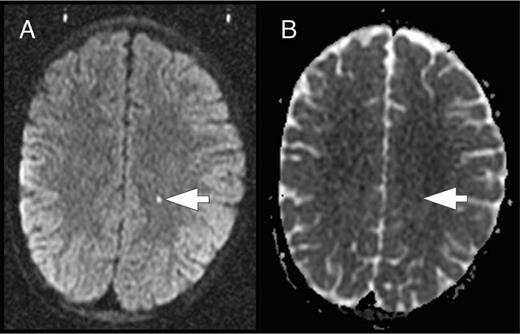

The brain is at constant threat of ischemic injury in sickle cell disease (SCD). The risk of overt stroke for children with SCD is more than 200 times higher than that for the general population, and this burden of overt stroke continues well into adulthood. An even more common form of neurologic injury in SCD is silent cerebral infarction (SCI), which has a prevalence of up to 40%. SCI refers to generally small, permanent brain lesions that are not associated with obvious focal neurologic signs (Figure 1). The term SCI is a misnomer because these strokes, even though they do not produce focal or localizing signs on neurologic examination, are often not “silent.” SCI is a morbid condition associated with neurocognitive impairment, poor academic performance, neurologic soft signs, and increased risk for subsequent overt stroke. Covert cerebral infarction may be a better descriptor, but SCI is the accepted term.

Figure 1.

SCI. Two typical SCI lesions (arrows) are shown in the frontal and deep white matter in a T2-weighted magnetic resonance image of the brain in a child with sickle cell anemia.